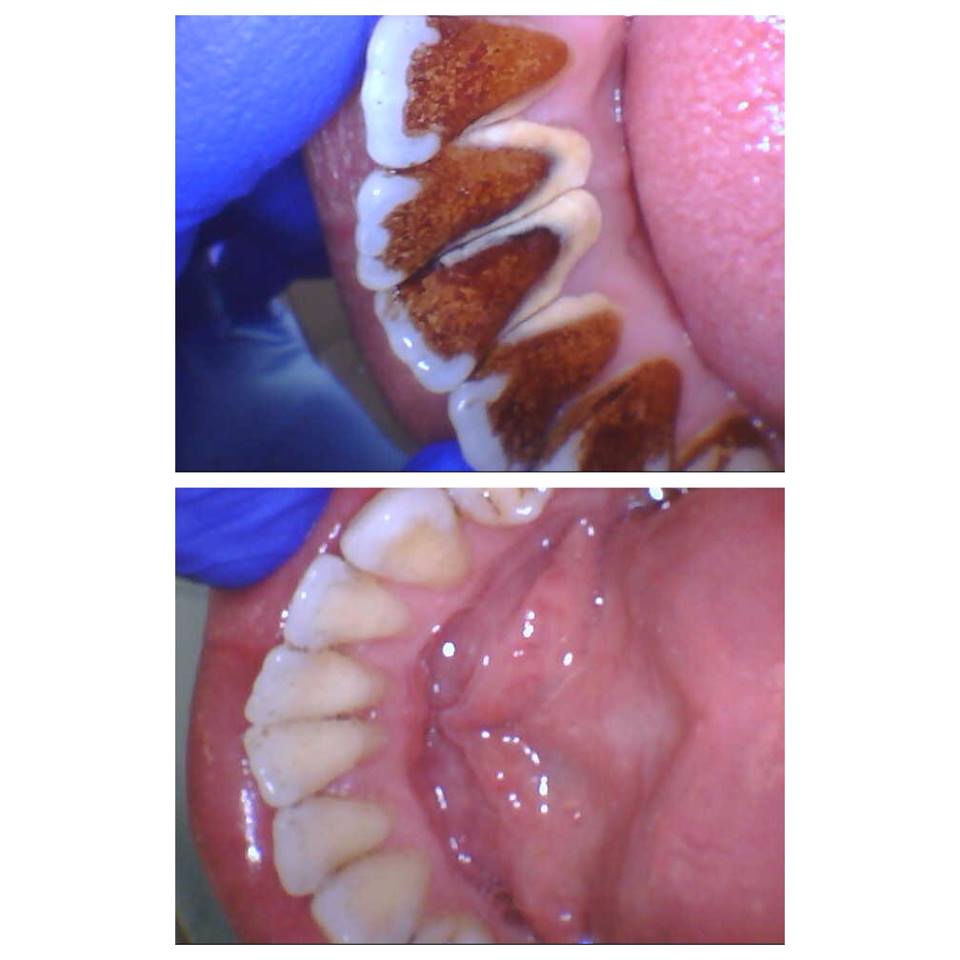

Photos of Nordic Dentistry